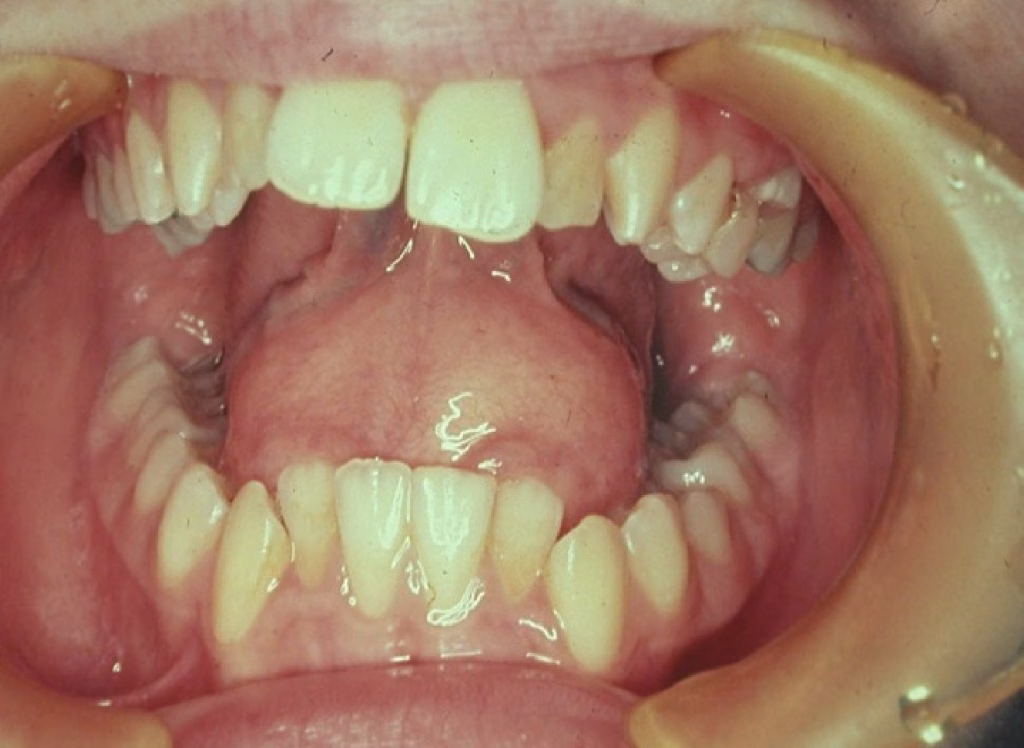

1. Simple Bone Cyst

A hollow space inside the jawbone.

What to know:

- Usually found in teens or young adults

- Often shows up by accident on an X-ray

- Teeth in the area stay healthy

- Rarely causes swelling

Treatment may involve surgically checking the area, but many heal on their own.